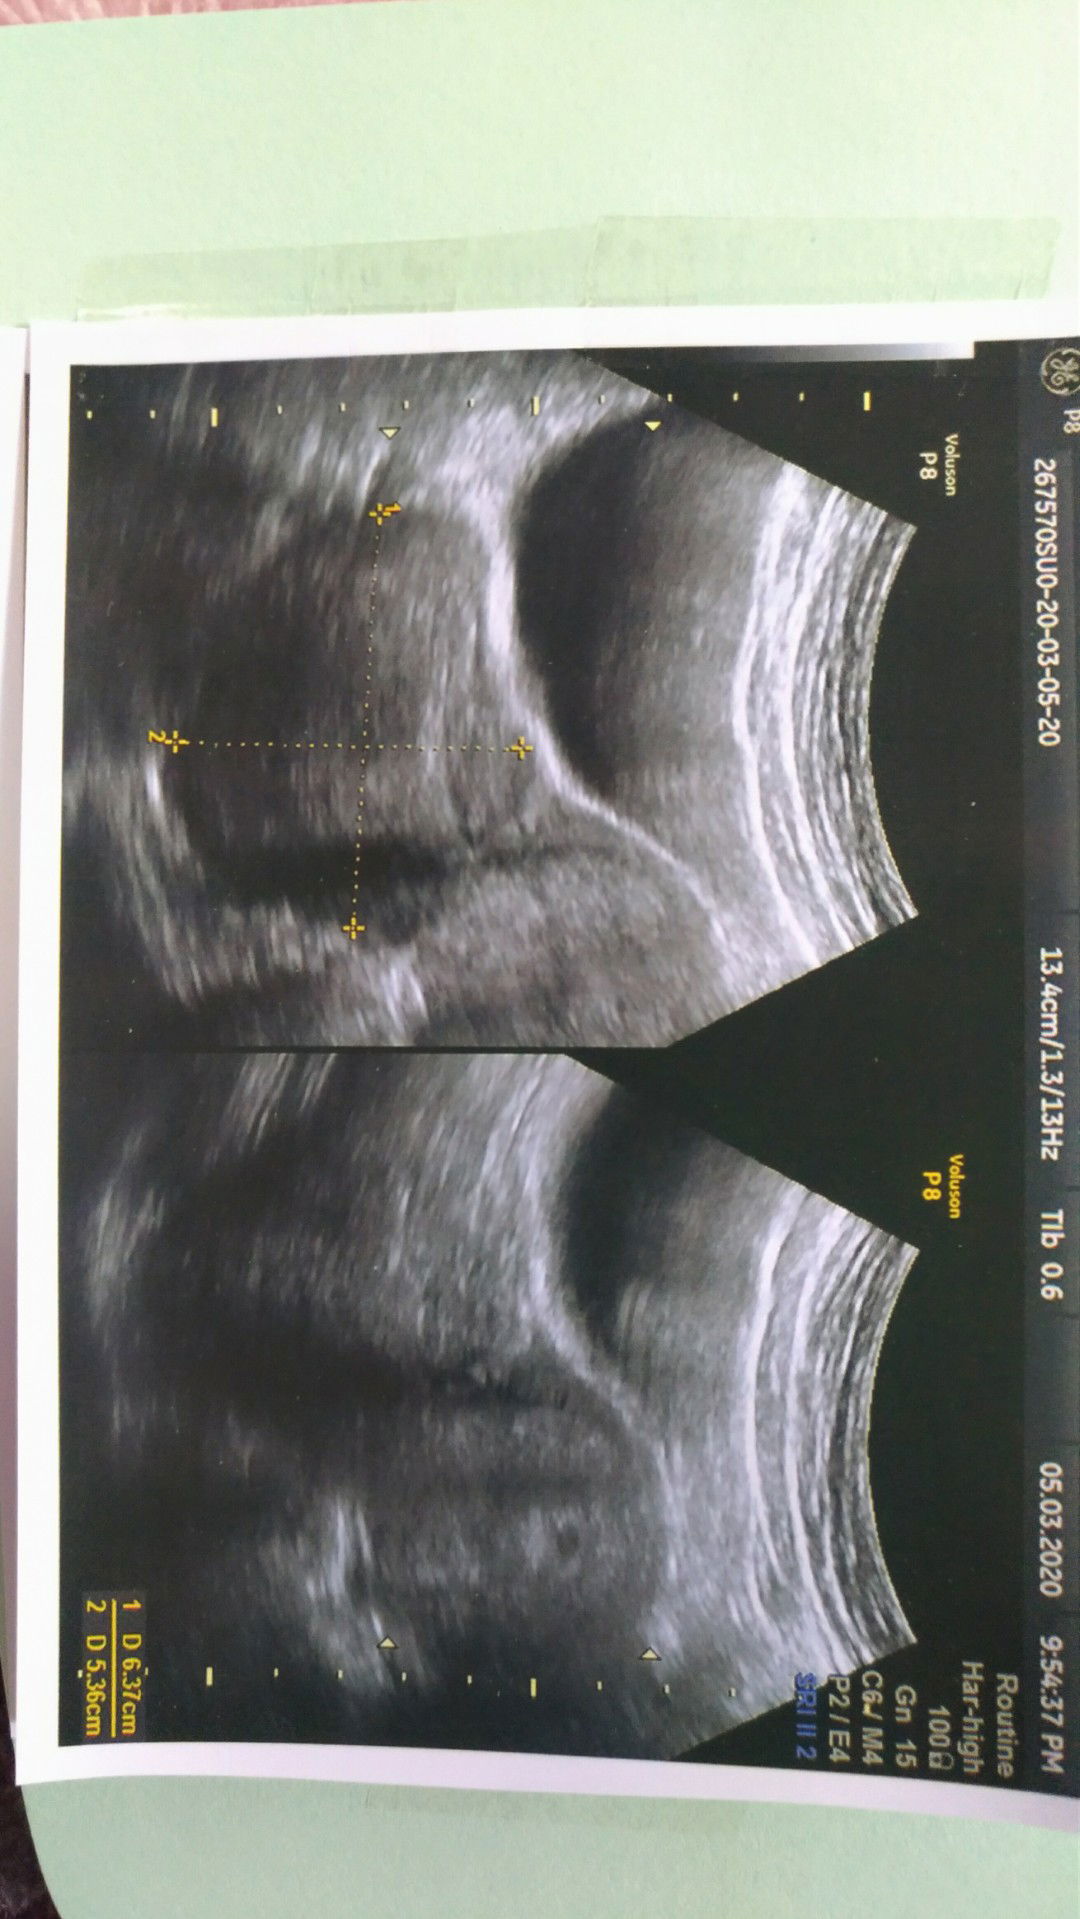

Hamil dan Tumor

Dua minggu yg lalu saya USG, dan terlihat ada tumor di perut saya sebesar 6cm, ternyata 2 minggu kemudian saya positif hamil. Sekarang usia kandungan 5 minggu. Semalam saya USG, kantong sudah terlihat, senang rasanya. Tetapi, tumor di perut bagian kanan juga semakin membesar. Dokter bilang, tidak perlu terlalu dipikirkan, tapi bagaimanapun sulit untuk saya tidak bersedih. Adakah bunda yang pernah mengalami hal serupa? Bisakah berbagi cerita dengan saya?